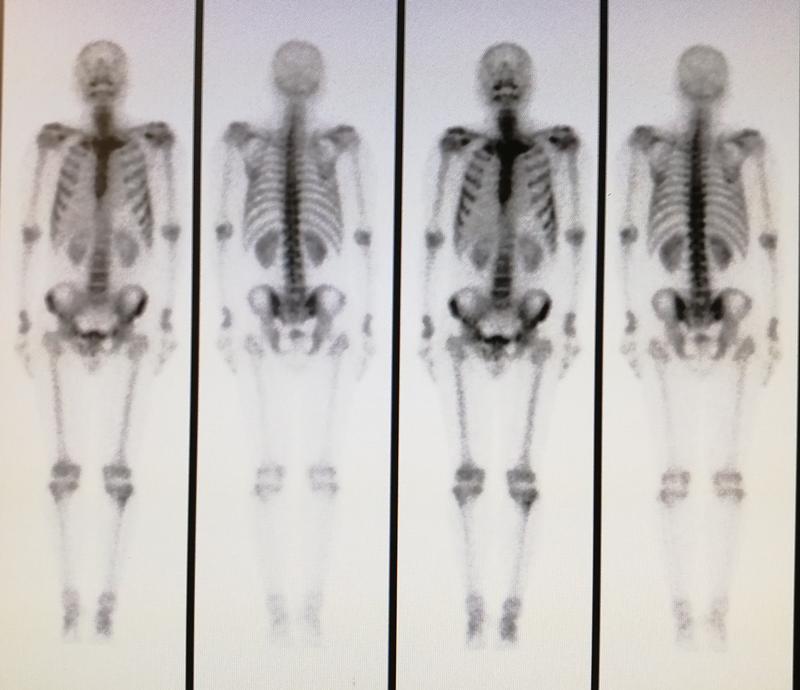

骨显像是核医学显像频率最高的检查之一,骨显像可以显示骨的形态、血液供应及代谢情况,能非常灵敏、无创伤的诊断骨疾病。全身骨显像是骨显像最常用的显像方式。

骨显像是将亲骨性显像剂(最常用的是99mTc-MDP)由静脉注射入体内并通过离子交换或化学吸附作用分布于骨骼组织,通过体外SPECT/CT仪探测其发出的射线,使全身骨骼显像。通俗的讲,全身骨显像就是静脉注射可与骨骼特异性结合的药物2到4小时后,通过相应的仪器探测发出的射线,使全身骨骼显像。

骨显像可以进行全身扫描而不增加额外的辐射剂量,对全身骨骼和病变的血流、代谢情况进行评价。放射性核素骨显像在诊断骨骼疾病方面具有灵敏度高、廉价、简便等优点,目前已成为临床核医学最具优势的项目之一。